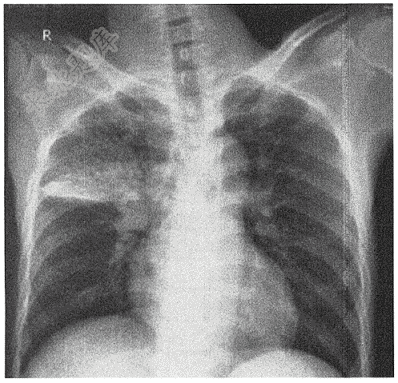

- 单项选择题男性,49岁,发热一周( )

A、右上肺炎症

B、右中肺大叶性肺炎

C、右肺中叶不张

D、右肺中叶结核

E、右肺上叶腺癌